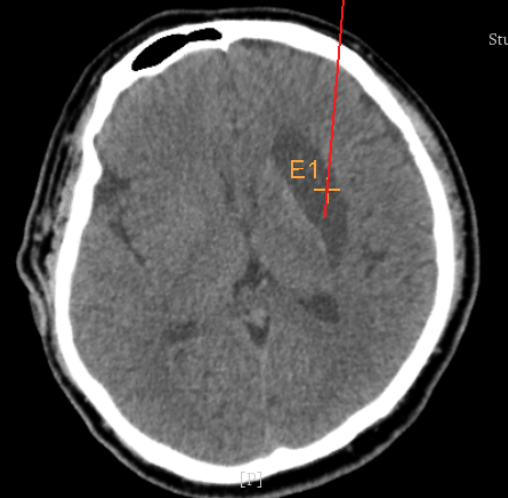

3個月前CT:腦出血

術(shù)前CT:血腫已經(jīng)液化,但仍有占位效應(yīng)